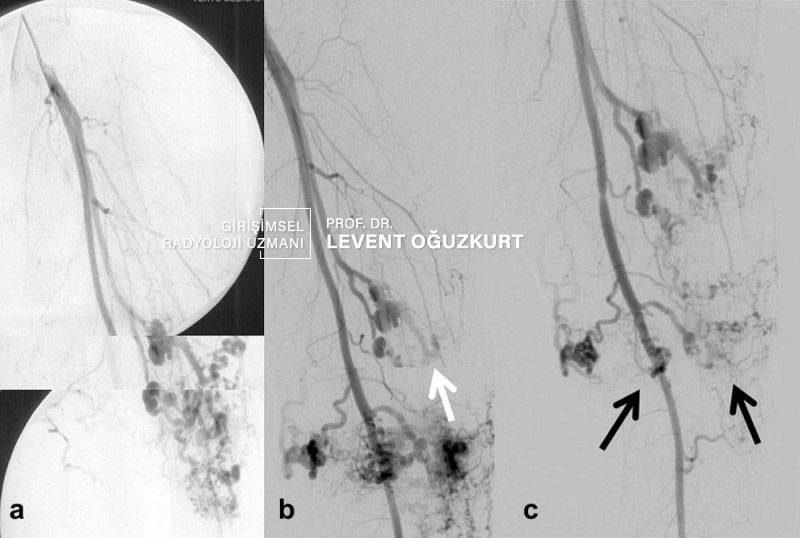

Arteriyovenöz (arteriovenöz) malformasyon içinde hem arter (atardamar) hem de ven (toplardamar) olan anormal damarsal oluşumdur. Kısaca AVM olarak adlandırılır. Vücudun beyin dahil bir çok bölgesinde görülebilir. Bu damarsal yapı genellikle doğumda vardır ama çok küçükse fark edilmeyebilir ve yıllar sonra büyüdüğünde ortaya çıkabilir.